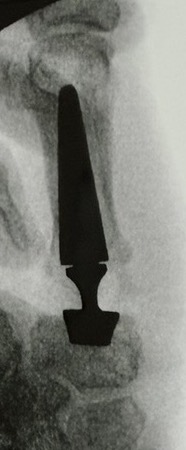

Arthroplasty

Options

Total joint arthroplasty

Spacer implants

Technique

Results

Tchurukdichian et al J Hand Surg Eur 2020

- 10 year follow up of 95 total joint replacement (IVORY prosthesis)

- 95% survival rate

- 7% dislocation rate

- 5% revision for fracture or dislocation

Smeraglia et al Int Orthop 2022

- 112 patients with pyrocarbon implant with mean 5 year follow up

- 7 year survivorship 95%

- subluxation rate 17%

- dislocation rate 3%